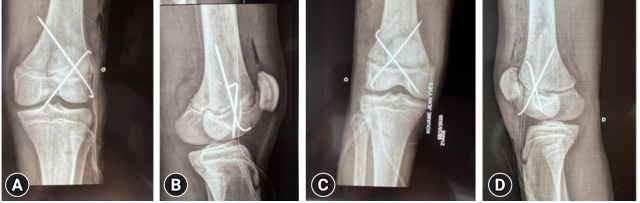

Epiphyseal dislocations and fractures frequently occur in children and adolescents. However, these injuries seldom involve the distal femur, and bilateral cases are even rarer. We present an unusual case of bilateral epiphyseal detachment of the femur in a 21-year-old man who was involved in a traffic accident. Open reduction and fixation surgery were performed 5 days after the incident. The patient experienced favorable progress, with consolidation occurring at 3 months. No lower limb length discrepancies were observed at the 20-month follow-up. In summary, bilateral distal femoral epiphyseal detachment is an uncommon condition that can be effectively treated through surgical intervention.